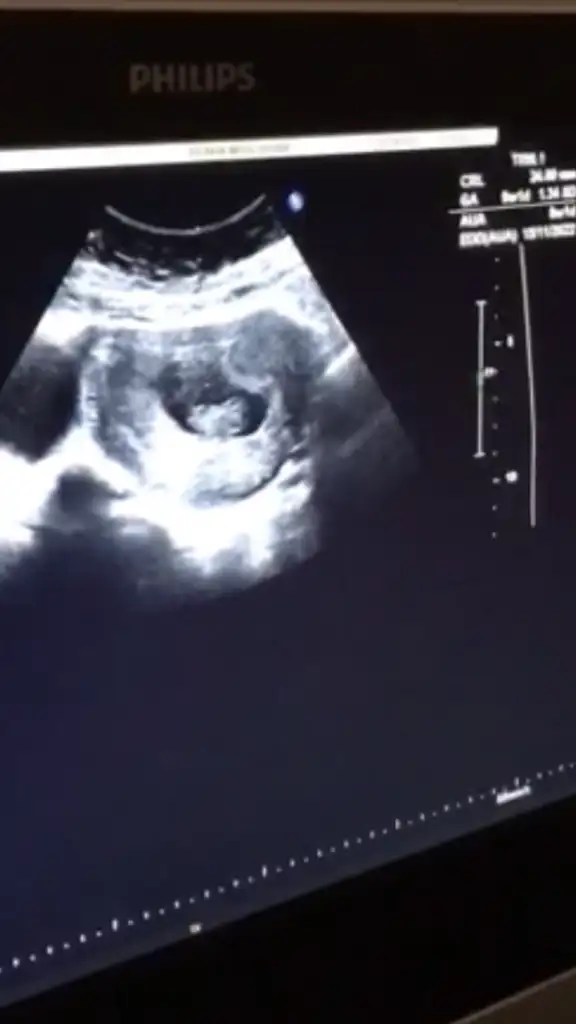

11.hafta erkek dedi çok büyük Ihtimalle . Baya emin konuştu diyebilirim. 17. hafta kız dedi. 29.unda detaylı ultrasonum var. Orda kesinleşir sanırım.

kuzu 11. hafta cinsiyet tahmini. için zaten çook erken doktorlar için. Bence 17. hafta tahmini %90 doğrudur. Ben sana ne tahminde bulunmuştum 🧐

Kız dedin sen direk 11.haftaya☺️ Kesinlessin iyice alışveriş yapicam ona göre bebişe 🤣😍